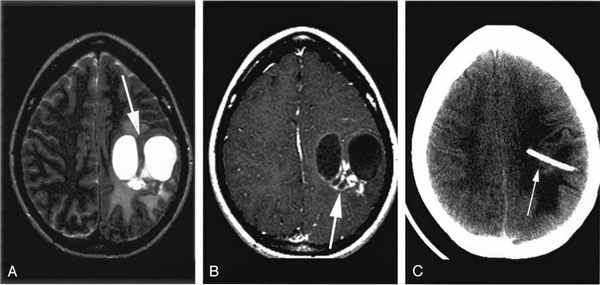

Предварительный диагноз ПМЛ ставится на основании данных МРТ с контрастом, выявившей единичные или множественные очаги поражения белого вещества на Т2-взвешенных изображениях. Контрастное вещество слабо накапливается, как правило, по периферии в 5–15% очагов. При КТ могут определяться очаги пониженной плотности, не накапливающие контраст, однако этот метод является менее чувствительным по сравнению с МРТ.

Киста головного мозга снимок МРТ

| Киста прозрачной перегородки на МРТ | Арахноидальная киста на МРТ |